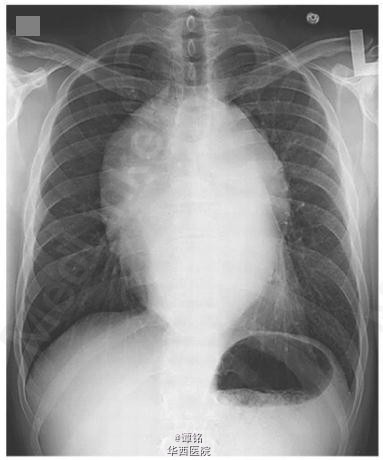

30岁男性,胸闷气紧、呼吸困难、吞咽困难、吞咽痛2月,体重减轻14kg。3年前查出I期睾丸精原细胞瘤,行睾丸切除术。此次胸片、CT显示后纵膈19*15*8cm的大肿物(图1,2),侵及邻近结构和降主动脉。hcG 4mIU/ml,LDH 1400/L,活检符合精原细胞瘤改变。采用博来霉素、依托泊苷、顺铂方案行3周期化疗,症状持续改善(随访三月,图3),见肿物逐渐缩小。10月后症状完全改善,后每4月长期随访。